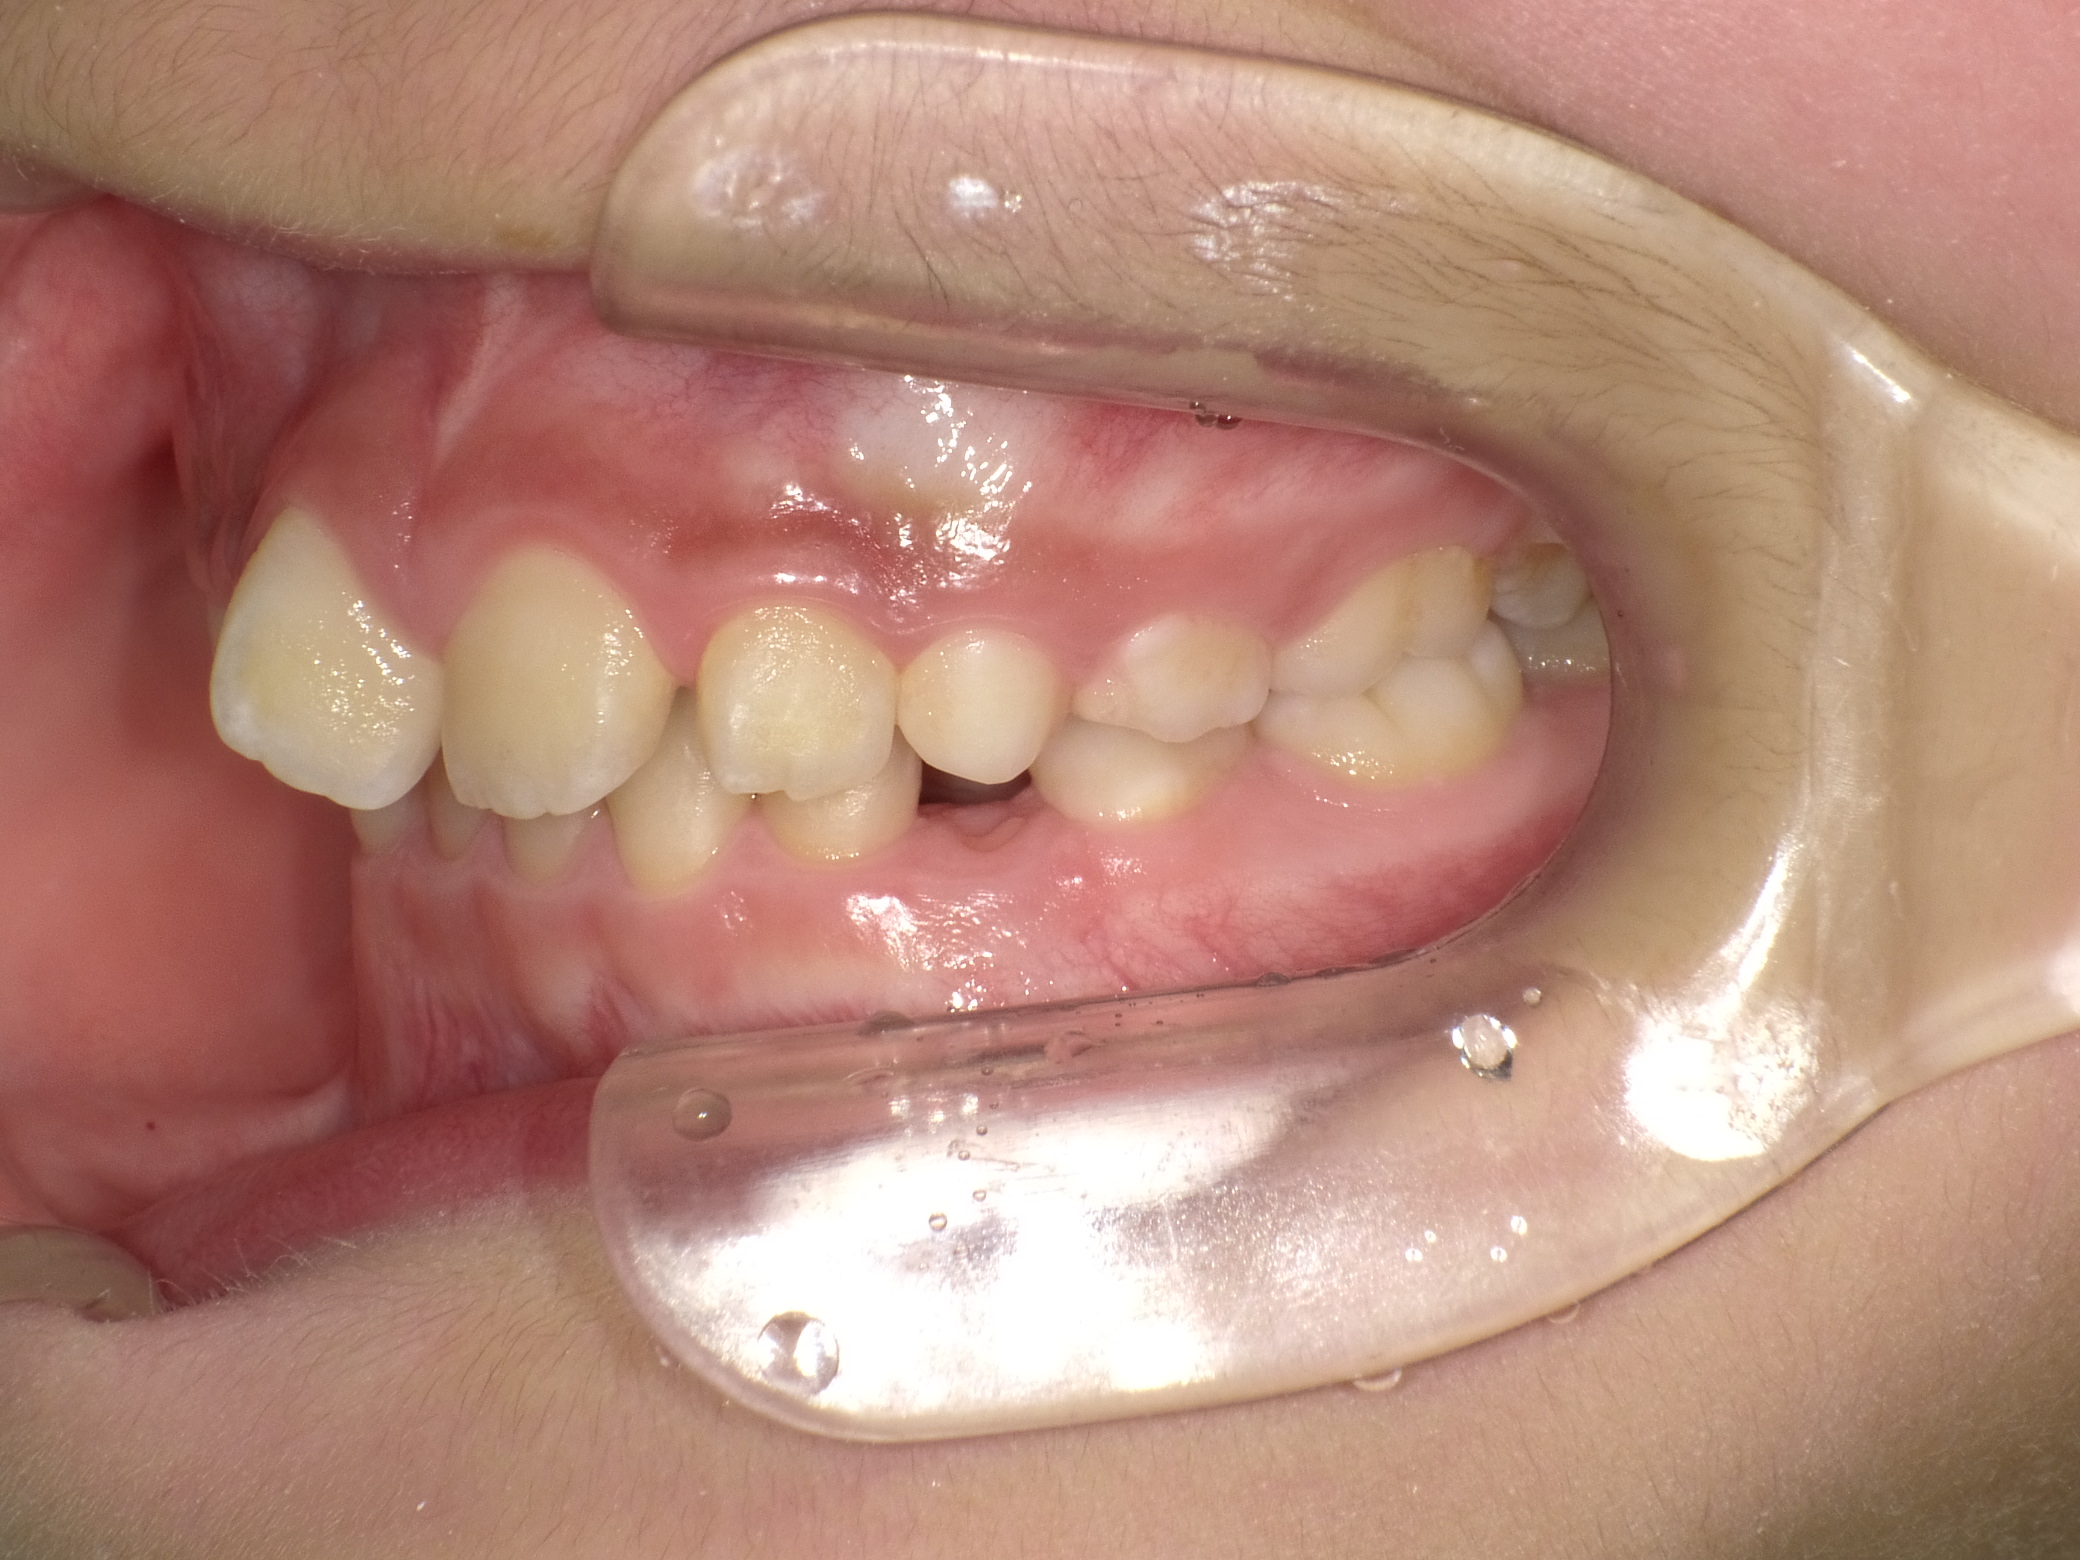

【小学生】マイオブレース矯正 上顎前突(出っ歯)と叢生(でこぼこ)を改善

小学生で開始

マイオブレース

でこぼこ

出っ歯

過蓋咬合

非抜歯

1期治療のみで改善

Before

After

治療期間

2.1年

治療開始

8歳

種類

マイオブレース矯正

使用装置

機能矯正装置

コメント

咬み合わせのズレを改善するために 矯正をされました

しっかり取り組んでくれてスムーズに終了しました